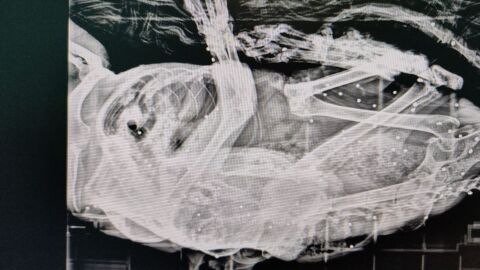

Ante la mala evolución del animal, llamado Van Gogh, fue trasladado al veterinario, donde las radiografías que le hicieron revelaron la presencia de decenas de impactos de perdigón en su interior. La Federación DEAN (Defensa Animal Cantabria), en la que se integra Gatucos Torrelavega, ha sido quien ha dado a conocer estos hechos.